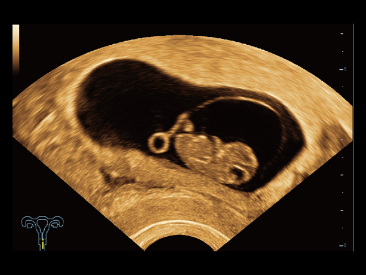

Desde que se fundó la compa?ía, Mindray ha explorado incansablemente nuevas formas de mejorar la confiabilidad del diagnóstico. Con la revolucionaria tecnología de ZONE Sonography?, la nueva plataforma ZST+ de Resona?7 lleva la calidad de la imagen por ecografía a un nivel superior mediante el procesamiento de datos de canal y la adquisición de zona.

Además de la calidad de imagen de primer nivel, Resona?7 también mejora las capacidades de investigación clínica con el revolucionario V?Flow para la evaluación hemodinámica vascular y con la adquisición de planos más inteligente a partir de conjuntos de datos 3D para el diagnóstico del SNC fetal. Al combinar el funcionamiento multitáctil basado en gestos más intuitivo y todas las características clínicas esenciales, Resona?7 realmente lidera las novedades en innovación de ecografías.